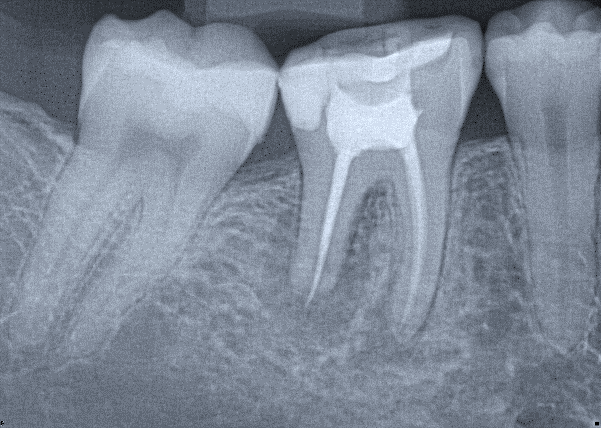

1.  (Select ONE OR MORE correct answers)

What observation(s) can be made for tooth 3.4?